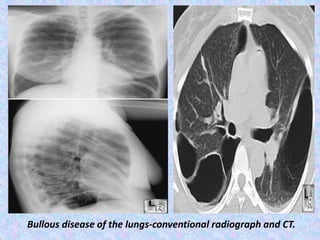

Bullous disease of the lungs-conventional radiograph and CT.

Abnormal air collections within the lung (focal bullae).

CT finding in emphysema is diagnosed by alveolar septal destruction and

airspace enlargement, which may occur in a variety of distributions.

Centrilobular emphysema is predominantly seen in the upper lobes with

panlobular emphysema predominating in the lower lobes. Paraseptal

emphysema tends to occur near lung fissures and pleura. Formation of giant

bullae may lead to compression of mediastinal structures, while rupture of

pleural blebs may produce spontaneous pneumothorax /

pneumomediastinum.